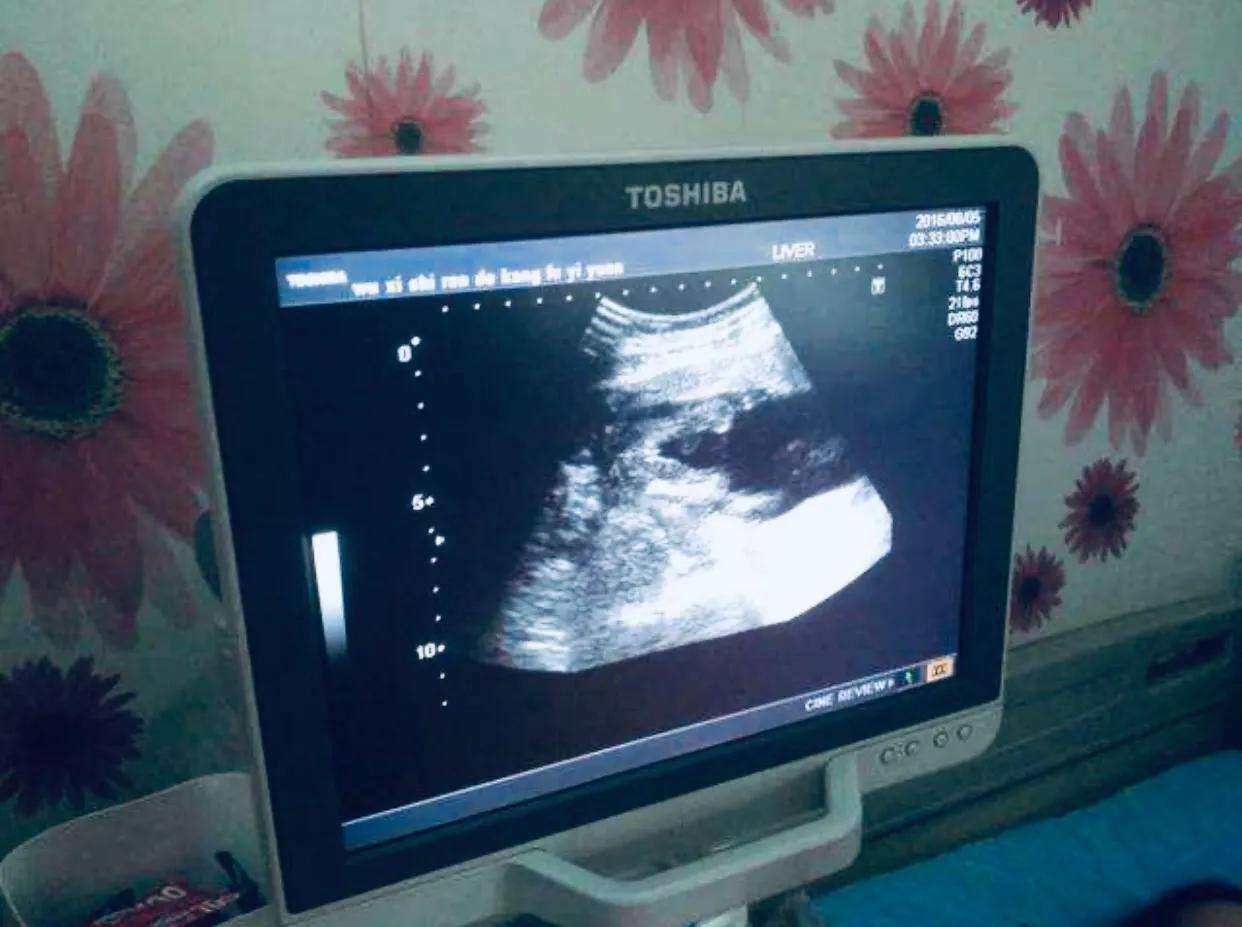

针对这几个流血原因,一般医生都会建议做彩超查看胚胎情况,排除宫外孕的可能,然后根据抽血查验的孕酮结果,开孕酮片或者打黄体酮针,直到不流血即止。

如果怀孕5周前彩超看不到的情况下,医生不建议强行保胎,普遍建议绝对卧床休息,定期来检查,直到能看到胎心胎芽为止。

经历过这段小心谨慎的孕早期后,就可以准备去做7周或8周的彩超检查了,看看胚胎发育情况,基本确定已怀孕,并趋于稳定。